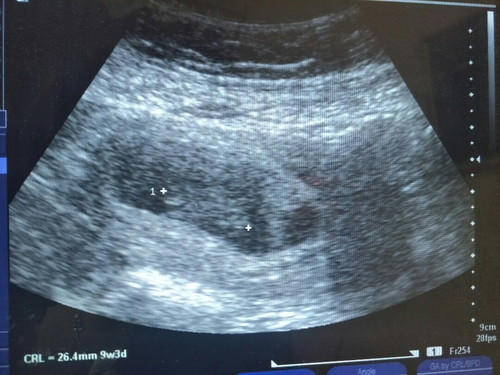

9 week

Alhamdulillah nampak jugak akhirnya.. sebelum ni scan 5 week xnampak dan doc siap tye (awak ngandung ke xni).. doc sendiri xkomfem sy ngandung ke x...perasaan sy masa tu Allah je yg tahu..sedih xterkata, saya ikhtiar 4 tahun 10 bulan...alhamdulillah akhirnye Allah bagi peluang saya mengandung.. Pada yang tengah usaha tu, teruskan usaha jangan putus asa.. Allah sentiasa ada dengan kita.. Bukan Allah xdengar doa kita, mungkin Allah dah buat rancangan yang baik untuk kita semua..